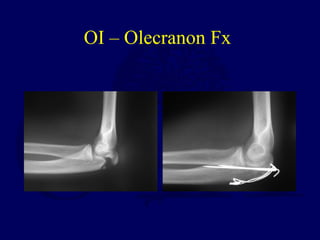

OI – Olecranon Fx